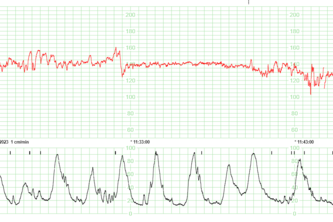

Hemos trabajado en un proyecto para detectar las diferentes características de los RCTG. Por ejemplo, detectar la frecuencia cardíaca fetal basal (FCFb), variabilidad, aceleraciones, etc.